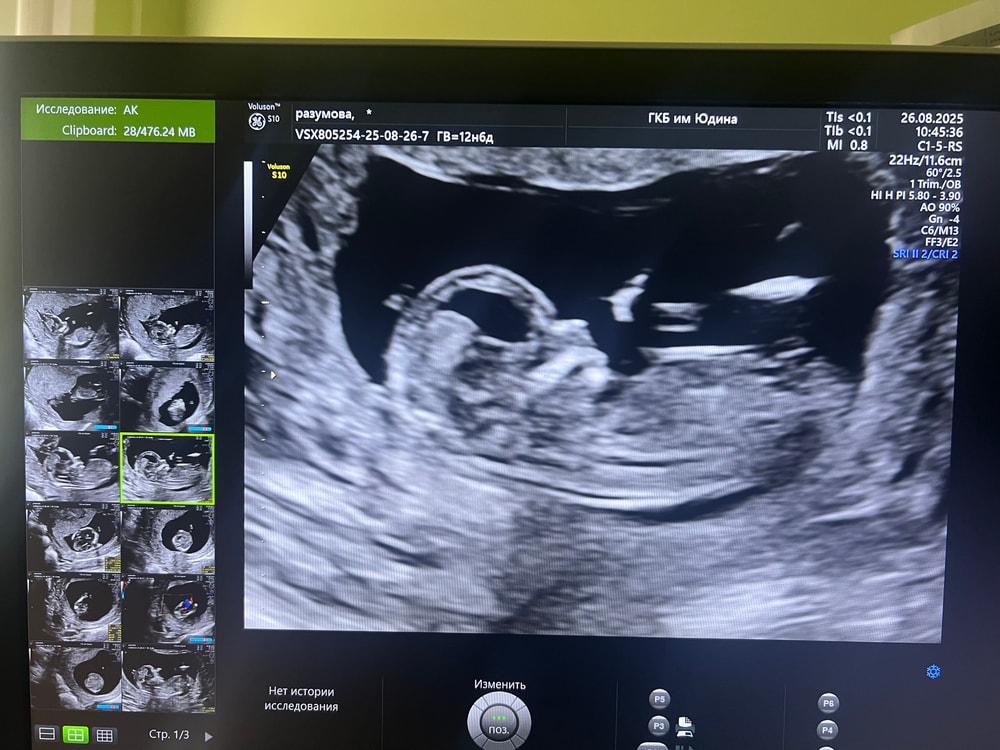

Пол малышаНу и я туда же)) через неделю второй скрининг,надеюсь скажут, читала,что как-то определяют по бугорку) фото со скрининга в 14 недель

Полина , вот я тоже думала,что это нога))фоткала с экрана,там стопкадры были,вот такое есть ещё